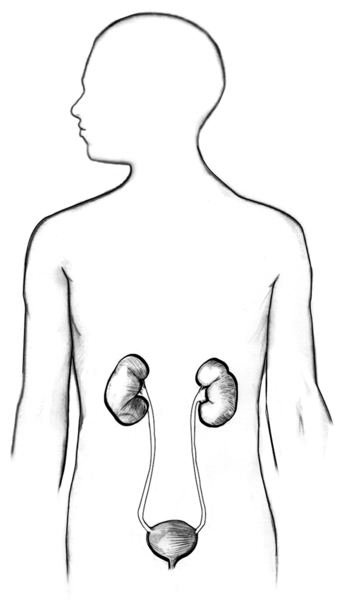

Drawing of urinary tract with kidney stones

Drawing of urinary tract with kidney stones.

Drawing of urinary tract with kidney stones.

Urinary tract with kidney stones